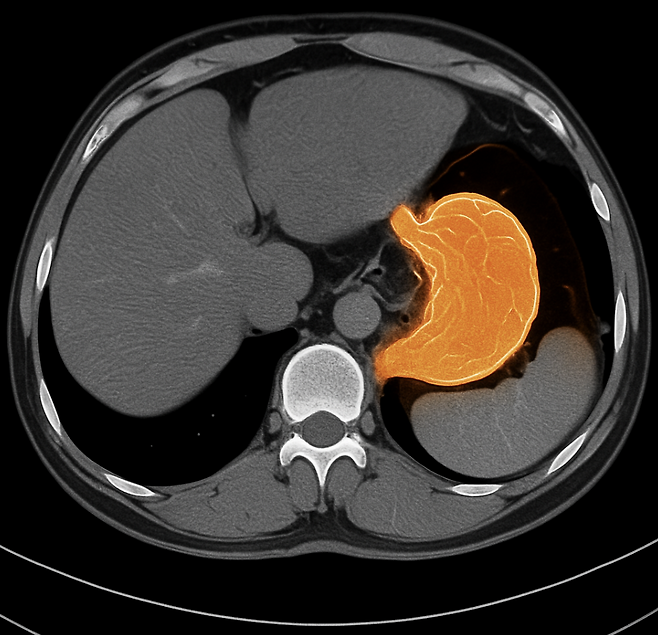

속이 더부룩하거나 체한 듯 답답한 증상, 단순 소화불량이라고 넘기고 계신가요? 사실 이런 변화가 반복된다면 위암 초기 증상일 수 있습니다.

위암은 초기에 뚜렷한 통증이 없어 놓치기 쉽지만, 몸은 이미 작은 신호를 보내고 있습니다. 오늘은 위암이 시작될 때 나타나는 대표적인 초기 증상 6가지를 알아보겠습니다.